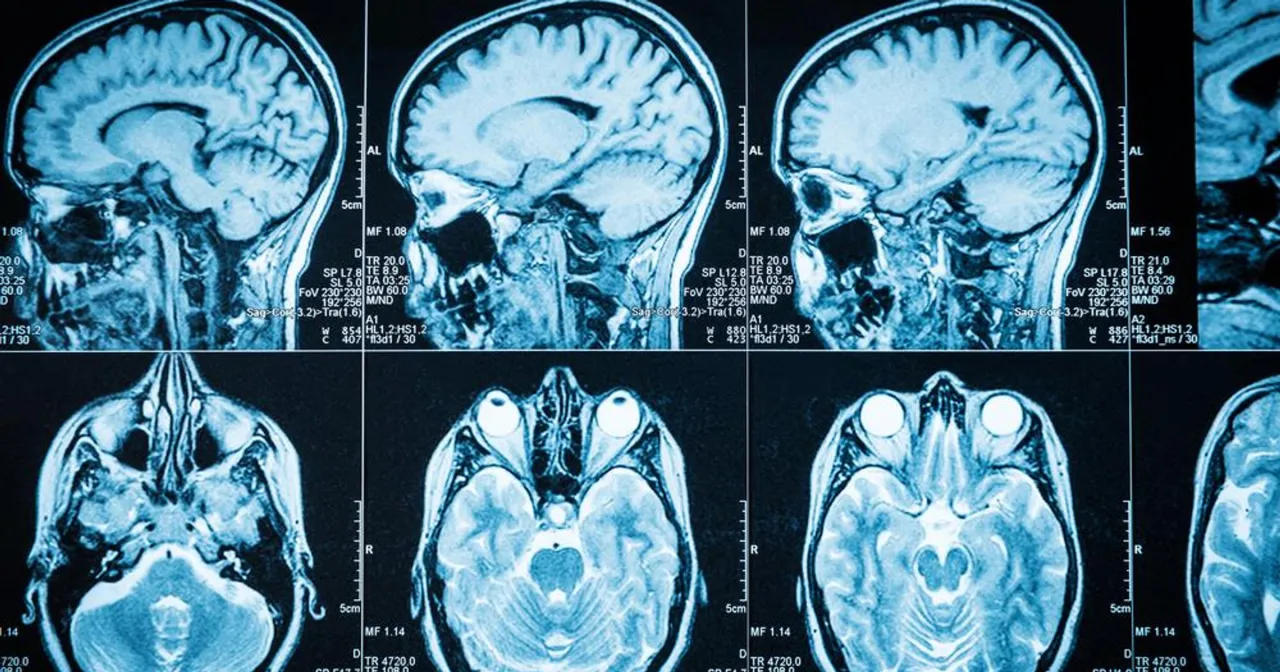

- Jak przygotować się do wizyty i jakie badania mogą zostać zlecone?: Przed wizytą u lekarza spisz wszystkie objawy: kiedy się pojawiły, jak często występują, jakie jest ich nasilenie i co je łagodzi lub nasila. To pomoże lekarzowi w szybszym postawieniu wstępnej diagnozy. Wśród badań diagnostycznych, które mogą zostać zlecone, kluczowe są rezonans magnetyczny (MRI) głowy z kontrastem oraz tomografia komputerowa (TK). MRI jest zazwyczaj preferowane ze względu na lepszą rozdzielczość obrazu i możliwość dokładniejszej oceny zmian w tkankach miękkich mózgu. Te badania pozwalają na uwidocznienie guza, określenie jego wielkości, lokalizacji i wstępnej charakterystyki.